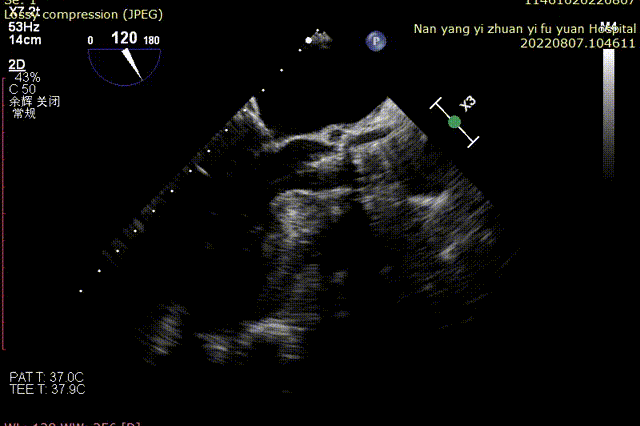

术前TEE超声:

20mm球囊预扩张:

球囊有明显腰征,无漏。